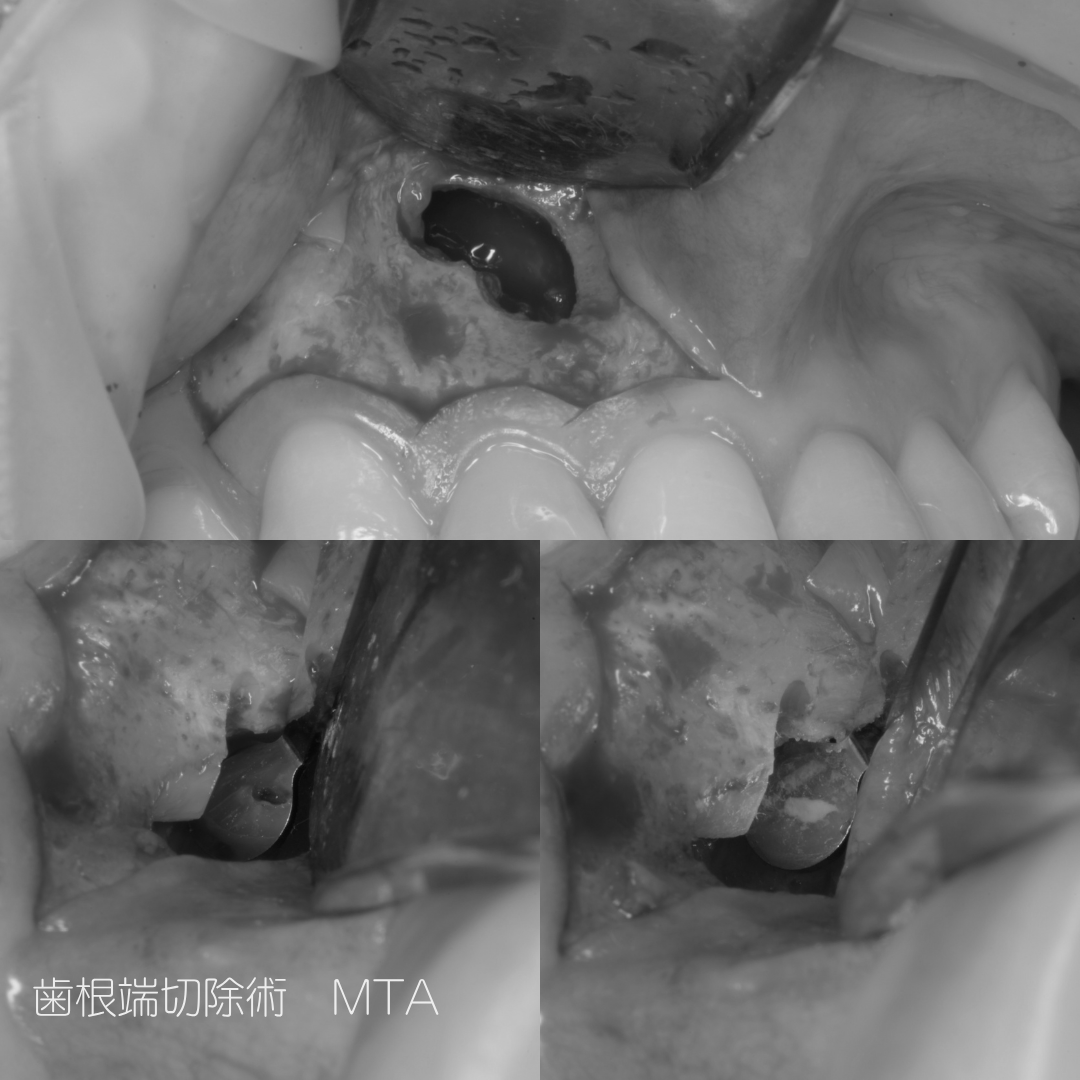

歯根端切除術とMTAセメントを充填

歯根端切除は歯根側からアプローチし、病巣を取り除きます。その後歯根の先端をカットし、MTAセメントを緊密に充填します。

※写真は出血などがあるため白黒にしています。